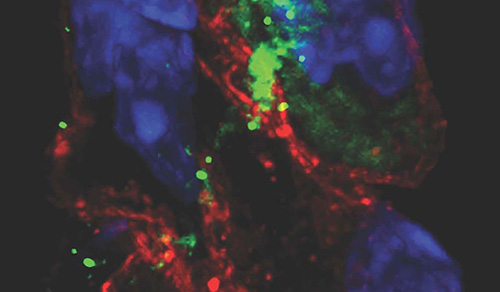

In 2025, cardiologists and cardiac surgeons at NewYork-Presbyterian led breakthroughs that impacted a range of diseases and conditions from advanced heart failure to pediatric valve disease. Physicians and researchers from Columbia and Weill Cornell Medicine pioneered the use of artificial intelligence to identify structural heart disease, launched a mobile app to expand access to heart failure education, performed one of the first split-root domino partial heart transplants, and more. Our experts remained at the forefront of innovative, multidisciplinary care, delivering comprehensive treatment for the most complex cardiac diseases.

Our world-renowned Columbia and Weill Cornell Medicine physicians and surgeons in our comprehensive cardiology, heart surgery, and vascular programs spearhead groundbreaking clinical and scientific research and provide the most innovative treatments to optimize patient outcomes for all stages of disease complexity. Our clinicians are experts in minimally invasive approaches and novel therapeutics for all types of heart disease and work across disciplines to provide compassionate care to all patients.